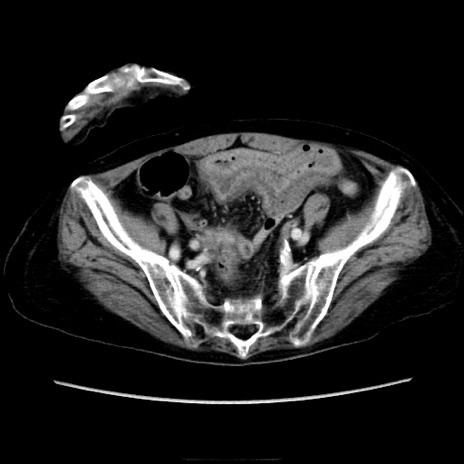

症例40(横断像)

【症例】90歳代女性

【主訴】腹痛・嘔吐

【現病歴】 食欲低下、嘔吐があり昨日他院受診。肺炎と診断され入院となる。入院後より腹部全体に圧痛あり。胃管留置され経過みていたが、症状持続するため、

当院転院となる。

【既往歴】胸椎圧迫骨折、胆石症

【身体所見】腹部:中央に激痛あり、圧痛あり、反跳痛不明

【データ】WBC 17100、CRP 18.82

横断像